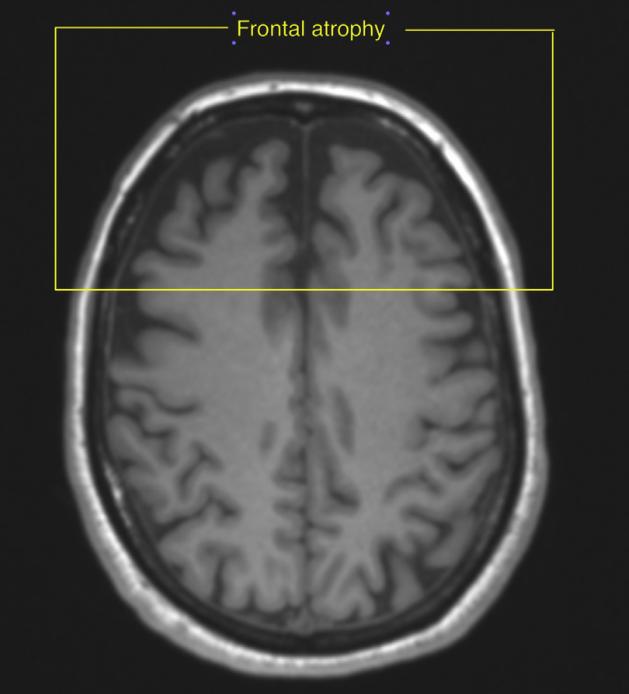

超剂量使用时为什么会有欣快的感觉?目前机制未名,研究者推测在高剂量时不仅仅激活了GABA-A受体的α1亚基(负责镇静),同时激活了GABA-A受体的α2亚基(负责改善焦虑),从而使人感到欣快、舒适。研究还发现唑吡坦成瘾者的大脑核磁共振扫描下额叶是萎缩的(黄色方框框起来的部分)。额叶负责记忆、判断、分析、推理等高级认知功能,研究发现这些患者在滥用后会出现注意力不集中、记忆力下降、执行能力下降,导致工作和学习能力下降。还有研究显示服用唑吡坦后出现了梦游、呓语以及遗忘。